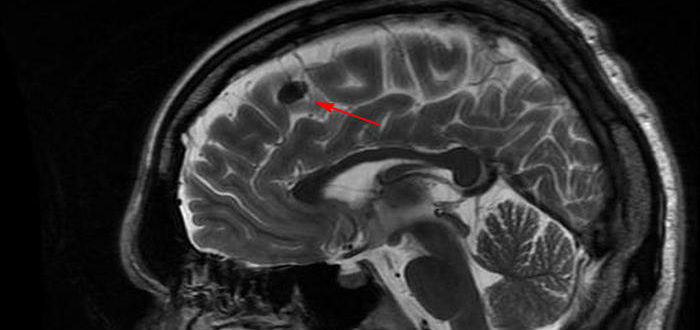

МР картина умеренно выраженной наружной гидроцефалии и точечная боль справа

Умеренно-выраженная наружная гидроцефалия у взрослого: что это такое, признаки Гидроцефалия – обильное скопление жидкости в головном мозге. При данном заболевании наблюдается интенсивная выработка спинномозгового секрета между смежными желудочками…